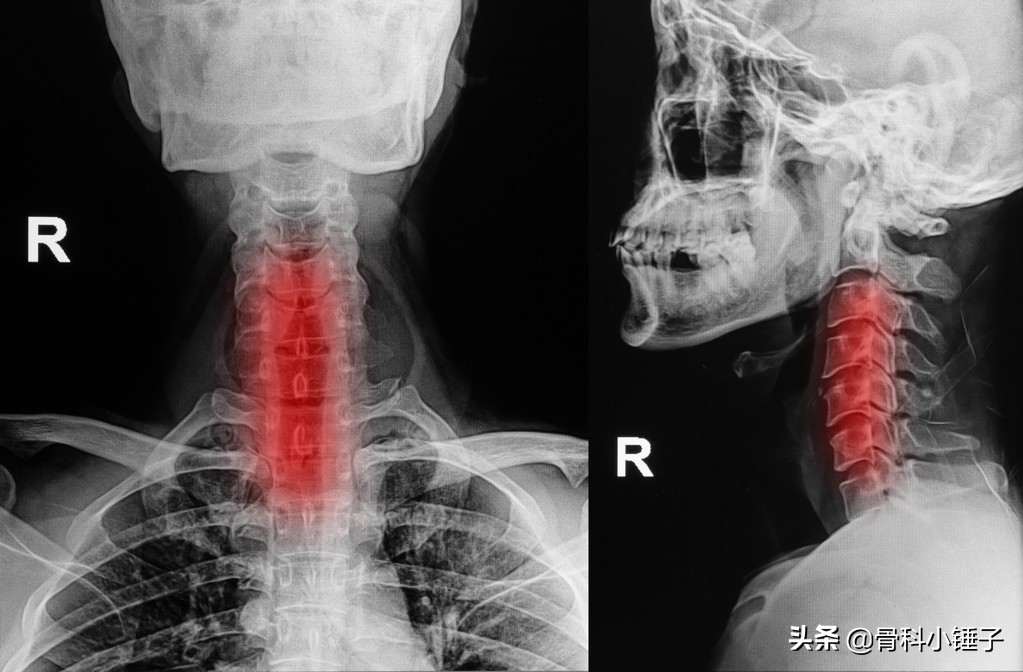

在业内,脊柱外科专家们已经达成共识,科学和合理的颈部锻炼可以有效缓解颈部的疼痛,而对于颈椎术后的病人来说,适量的颈部肌肉抗阻练习也可以提高颈椎的稳定性,使患者更快更好的回到正常生活中去。

如果说颈椎就像故宫里最重要的太和殿,那颈部肌肉就是一层层外围的城墙,紫禁城里的城墙越厚实,越坚固,中心地带就越安全越稳固。就好比你是很难想象像图中这些拥有发达颈部肌肉的运动员,他们会得颈椎病一样。